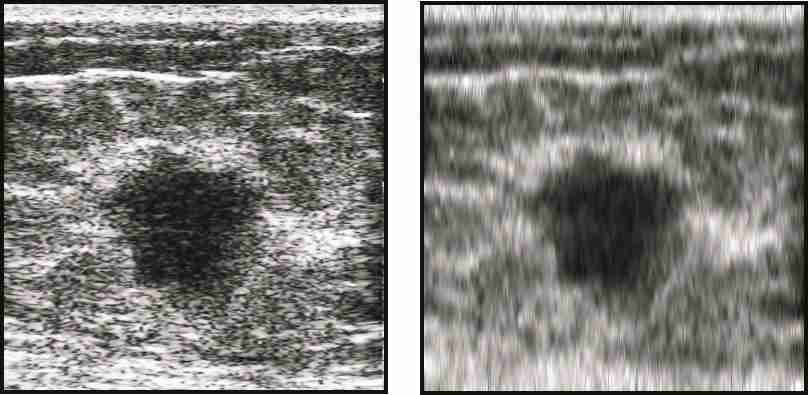

Invasive ductal carcinomas generally have fuzzy borders as a result of having invading margins. On the contrary, cancers that elicit little desmoplastic reaction (proliferation of fibroblasts) typically have clear margins, but are highly irregular in shape. We define Margin Definition as the sum of the magnitude of the gradient of on a lesion contour normalized by the sum of magnitude of on the lesion contour [33]. Although this feature uses both the lesion contour as well as a spectral parameter, we used this as a spectral feature. As is statistically well-behaved, is relatively speckle-free, and can more easily be corrected for system effects and diffraction, the midband fit image was used instead of the B-mode (envelope of RF echoes) image. Benign lesions exhibit greater value of gradient-based margin definition. Figure 3.2 shows two lesion images with sharp & fuzzy borders and shows their gradient images that are used for calculating margin definition. The lesion with sharp border gives the value of and the lesion with fuzzy border gives the value of .